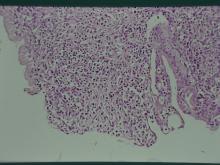

低倍鏡下,長期持續大量的子宮蓄膿使子宮肌層變薄,子宮內膜覆蓋上皮外受

損消失,粘膜層呈現顯著炎症反應(圖7),高倍鏡下可見到喪失上皮覆蓋的

粘膜呈現顯著的炎症反應(圖8)。四、 實驗室檢驗: 病例 血液學檢查 血液生化學檢查 微生物分離 1 1.WBC上升(中度)